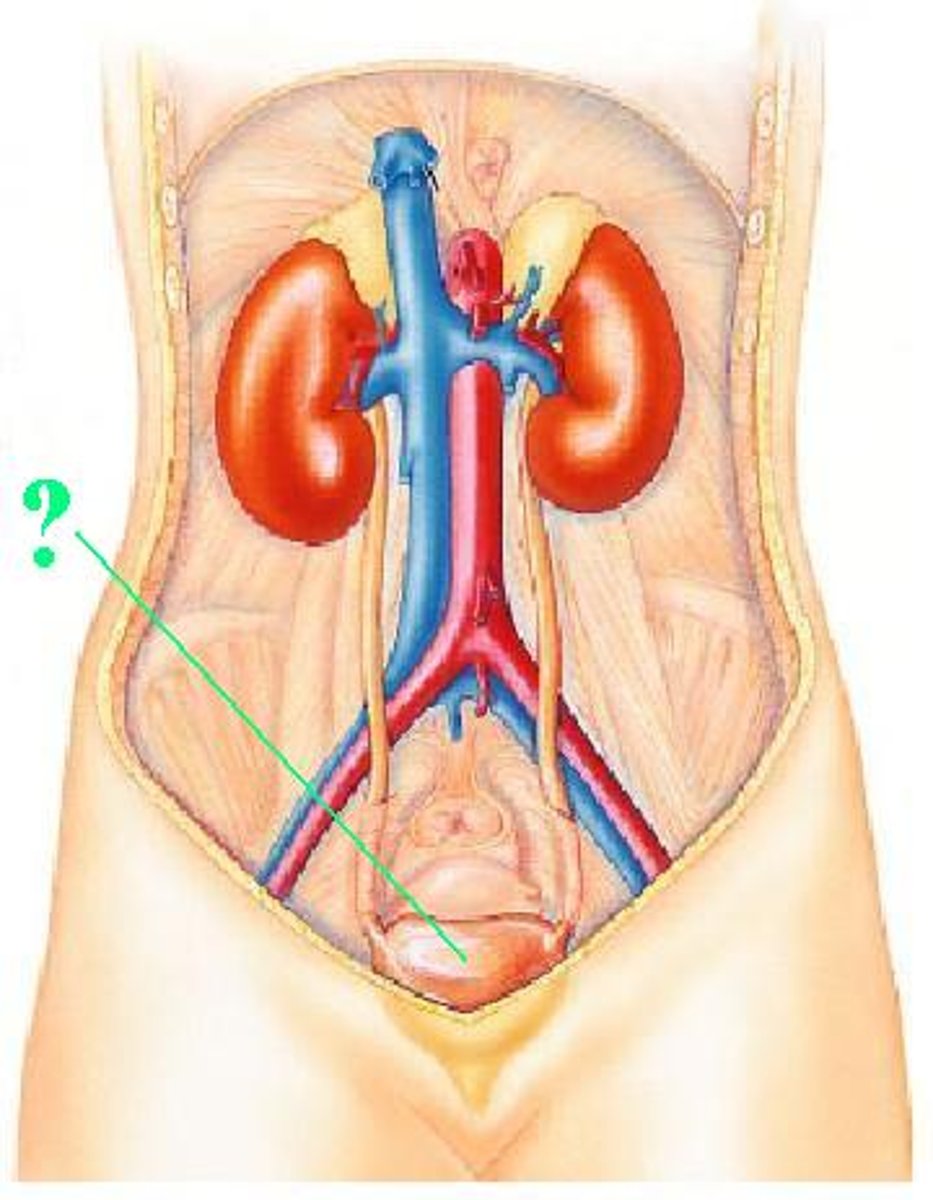

urinary bladder

Identify the indicated structure.

ureter